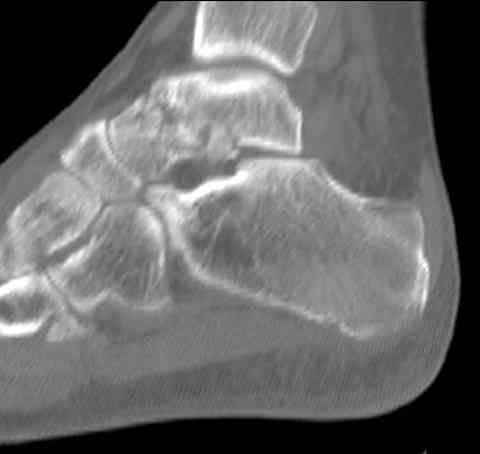

а основании двух видов ренгенограмм невозможно радикально решить о необходимости открытой репозиции или первичного артродеза.

Для оценки состояния нужны дополнительные исследования, например Canale или Broden ренгенограммы и Компьютерная томография.

При переломах тарана всегда имеется риск AVN, а классификация Hawkins поможет разобраться с предполагаемыми осложнениями.

Если в первом типе, когда перелом шейки без смещения, тогда AVN менее 10%, при втором типе когда имеется смещение и вывих тарана в субталарном сочленении меньше 40%, а при типе III когда смещение в голеностопном и субталарном суставах - около 90% и в типе IV, когда происходит полный вывих, риск AVN достигает 100%.

Для оценки состояния нужны дополнительные исследования, например

повторили рентгенограммы и доделали проекции, к единому мнению все еще не пришли

На ренгенограмме не уловил многоскольчатость тарана, чтобы доказать, конечно, можно было исследовать на КТ, потом КТ дает ориентацию фрагментов.

Два фрагмента суставной поверхности тарана можно восстановить боковой компрессией шурупами и дополнительно костная пластика.